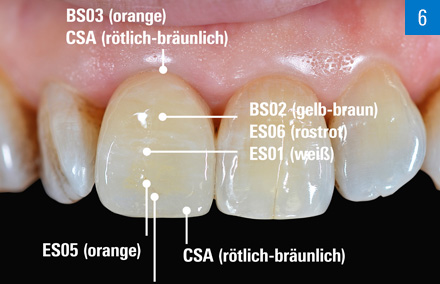

Détermination de la couleur de la dent, sélection du bloc et caractérisation pour l'effet de couleur approprié d'une seule facette antérieure en VITABLOCS Mark II.

Une histoire à succès : facette antérieure en VITABLOCS Mark II

Situation initiale

Une jeune patiente d'une vingtaine d'années présentant une décoloration post-traumatique de l'incisive centrale supérieure droite.

Solution

Afin d'obtenir une esthétique parfaite, la sélection du bloc a tenu compte non seulement de la couleur souhaitée de la centrale voisine saine, mais aussi de la décoloration de la surface de la dent préparée. Après le scan de la préparation mini-invasive, une facette monolithique en VITABLOCS Mark II 0M1 a été conçue et usinée.

Pourquoi choisir VITABLOCS Mark II ?

Grâce à l'esthétique naturelle intégrée, à la translucidité et à la fluorescence de la céramique feldspathique VITABLOCS, semblables à celles des dents, nous obtenons les meilleurs résultats monolithiques dans le flux de travail numérique. Dans ce cas, nous avons utilisé un bloc 0M1 pour compenser la couleur sombre de la dent préparée. Nous avons choisi VITABLOCS Mark II parce que cette couleur n'était pas encore disponible pour VITABLOCS TriLuxe forte à ce moment-là.